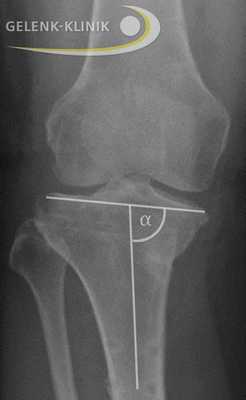

Анализ оси нижней конечности перед операцией, когда пациент стоит. В данном случае наблюдается варусная деформация голени с перегрузкой медиальной внутренней стороны сустава. © Gelenk-Klinik

Сначала проводится клиническое обследование, во время которого ортопед собирает всю информацию касательно имеющегося дефекта коленного сустава. Затем он осматривает ногу пациента и примерно определяет ось конечности. Рентген от бедра до ступни позволяет точно установить степень отклонения. На основании полученных снимков врач может планировать операцию.